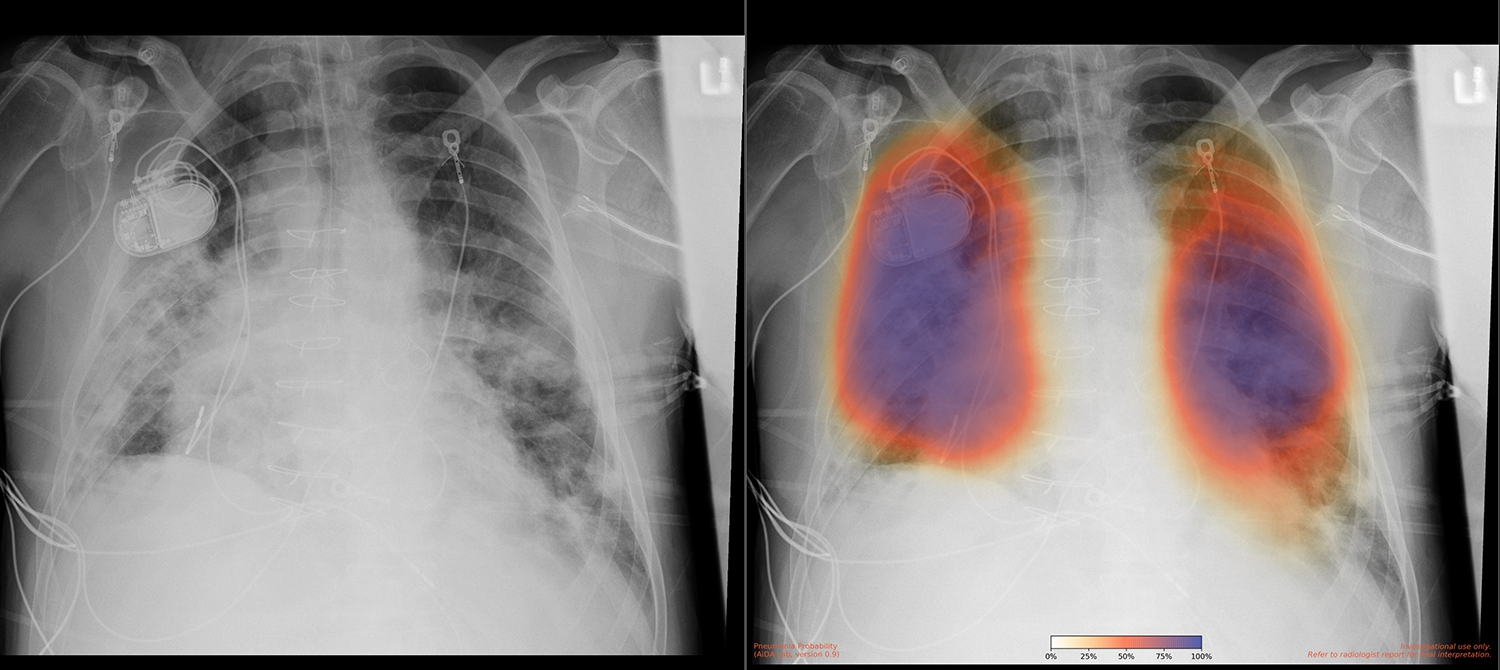

加州大學(xué)圣地亞哥分校健康中心是全球排名前15位的研究型大學(xué)之一。加州大學(xué)圣地亞哥分校醫(yī)學(xué)院每年進(jìn)行數(shù)百項(xiàng)臨床試驗(yàn),加州大學(xué)圣地亞哥分校健康服務(wù)研究中心專門從事健康結(jié)果數(shù)據(jù)的收集和分析,以支持研究。2018年,由加州大學(xué)圣地亞哥分校醫(yī)學(xué)院放射學(xué)副教授Albert Hsiao博士領(lǐng)導(dǎo)的加州大學(xué)圣地亞哥分校健康中心一個(gè)團(tuán)隊(duì)開發(fā)了一種使用機(jī)器學(xué)習(xí)在X射線圖像中檢測(cè)肺炎的方法。“我們創(chuàng)建了一個(gè)帶有顏色編碼的概率圖,表明肺炎的不確定性或確定性,”蕭醫(yī)生團(tuán)隊(duì)的住院醫(yī)師Brian Hurt博士說。根據(jù)Hsiao博士的說法,“人們通常做的是創(chuàng)建一個(gè)模型,給出一個(gè)簡(jiǎn)單的是或否輸出,表明它是否是肺炎。但我們認(rèn)為,制作圖像對(duì)于突出異常位置非常重要。該團(tuán)隊(duì)在2020年初發(fā)表了一篇關(guān)于這些結(jié)果的論文。

COVID-19 肺炎患者的胸部 X 線檢查、原始 X 線檢查(左)和肺炎 AI 結(jié)果(右)?;颊哂幸粋€(gè)起搏器裝置和一個(gè)擴(kuò)大的心臟,這表明人工智能算法足夠強(qiáng)大,即使患者有潛在的健康問題也能工作。